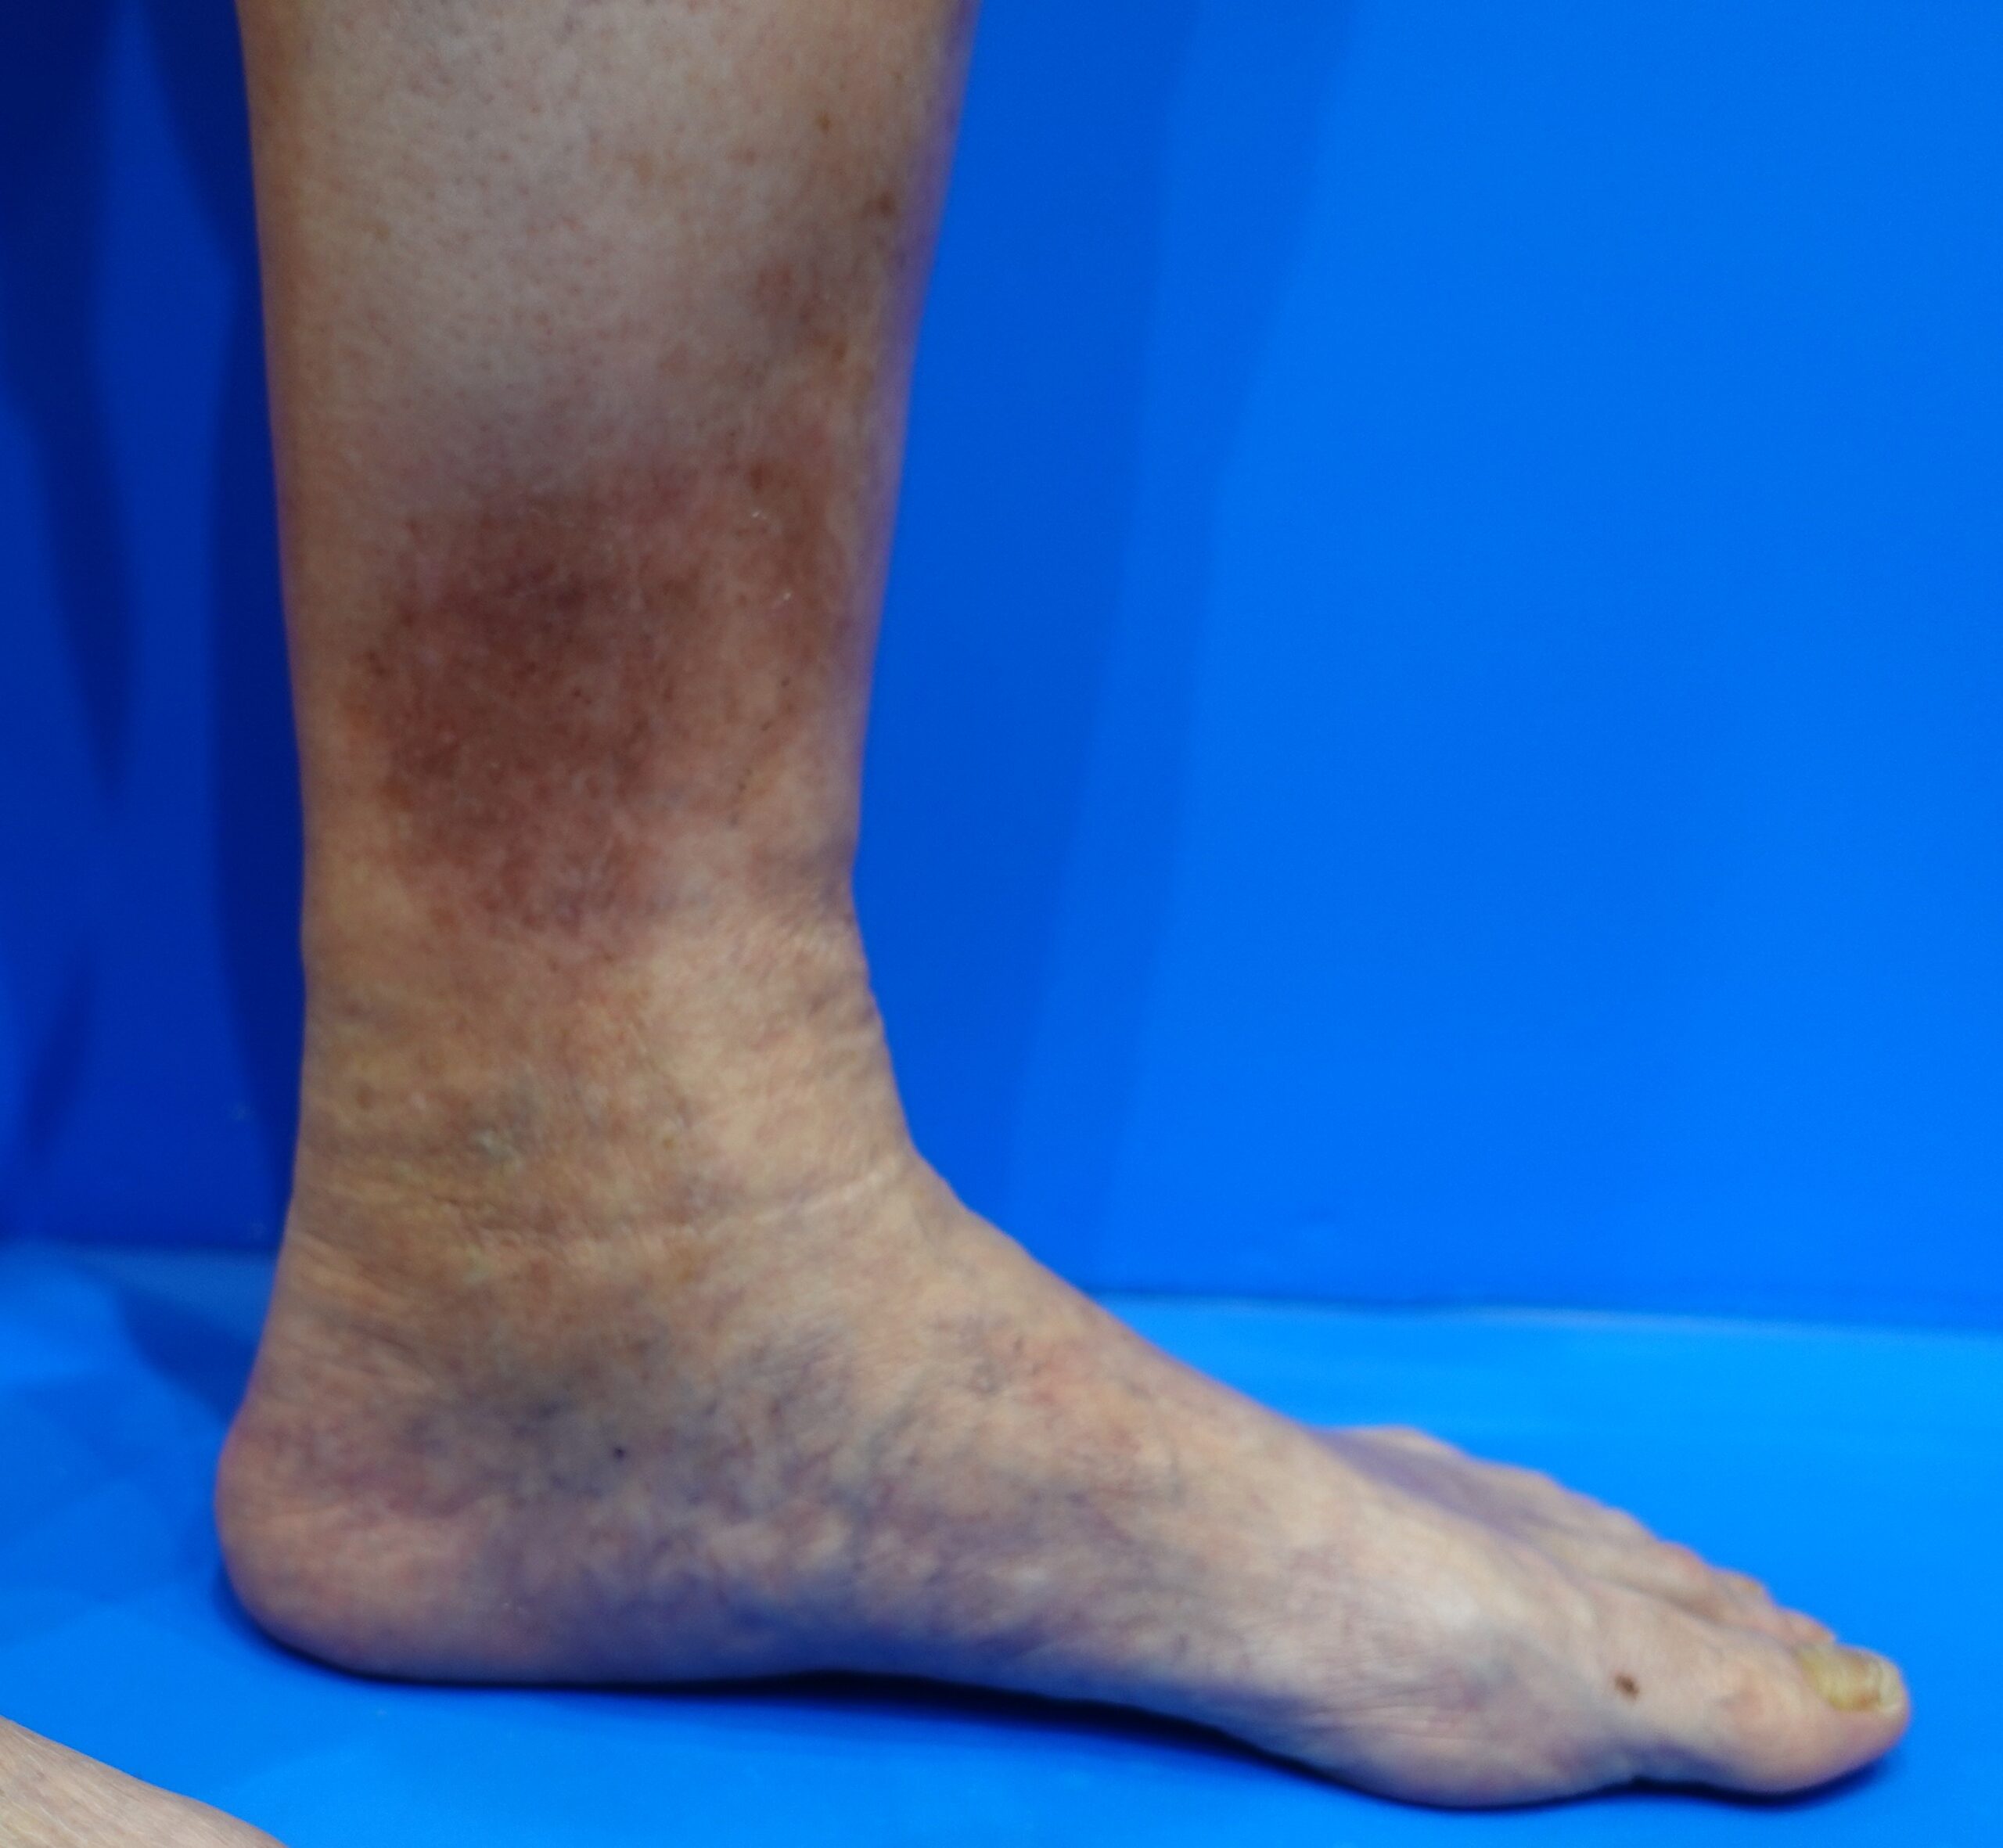

うっ滞性皮膚炎 色素沈着